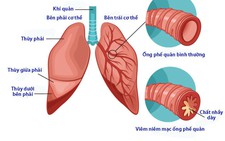

Lương y Hoàng Duy Tân, nguyên phó chủ tịch Hội Đông y Đồng Nai, cho biết viêm phế quản là tình trạng viêm hoặc tắc nghẽn trong các ống phế quản. Các ống phế quản kết nối cổ họng, khí quản đến phổi, phế nang.

Phế nang là túi khí trong phổi, nơi không khí được trao đổi giữa cơ thể và máu, phổi, môi trường. Oxy và các loại khí khác được hít vào và carbon được thở ra. Chất nhầy gây kích ứng và nhiễm trùng phế quản.

Viêm phế quản thường là kết quả sau khi bị nhiễm vi rút, vi rút gây cảm lạnh thường gây viêm phế quản cấp tính. Ngoài ra, viêm phế quản còn được hình thành và phát triển do nhiễm trùng từ việc hít phải khói thuốc lá, và thậm chí cả từ việc tiếp xúc với chất kích ứng trong gia đình và các chất gây ô nhiễm đường phố.